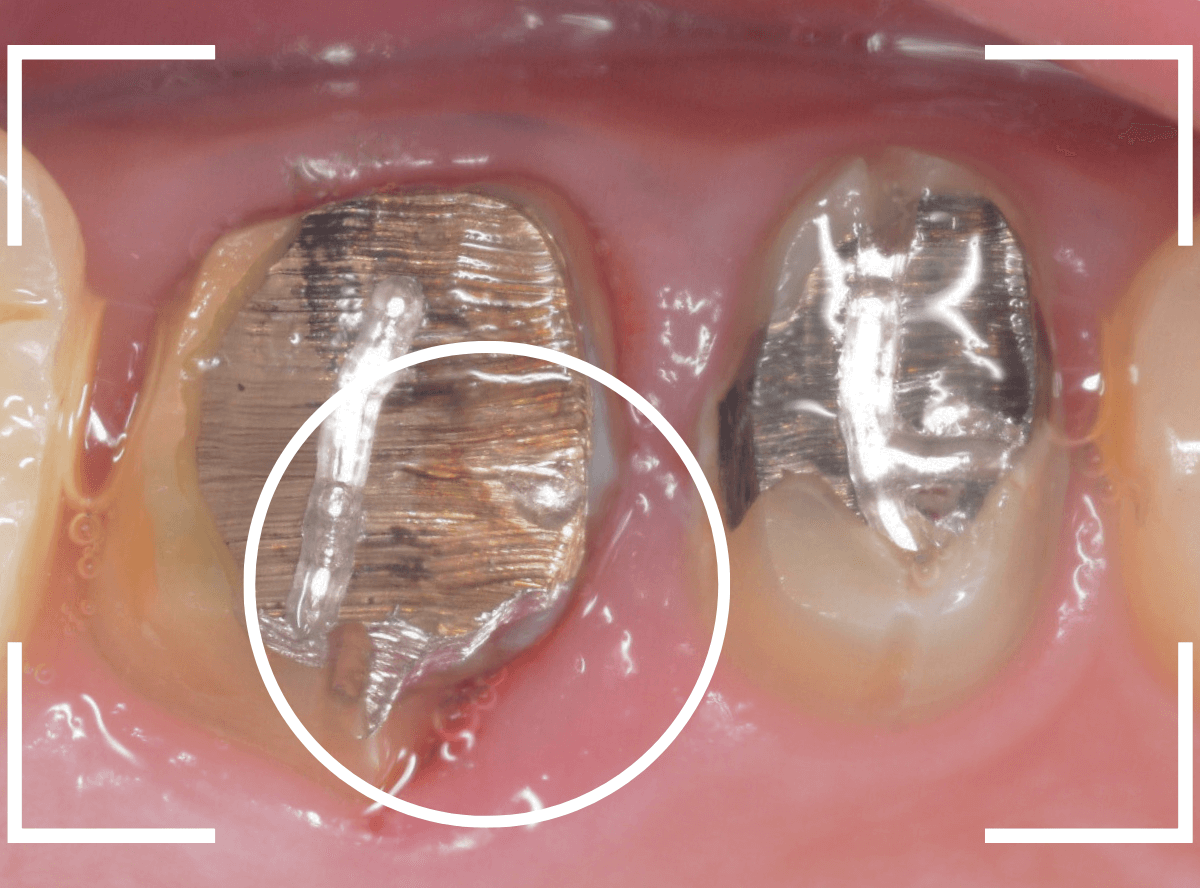

メタル・インレーとメタル・クラウンが入っていますね。

まずは、奥のメタル・クラウンを外します。

メタル・コアが入っていますが、こちらも慎重に外して、中を調べていきます。

レントゲン写真では問題なさそうでしたが、メタルコアを除去すると、中は真っ黒でした。

このように、コアの中で虫歯が進行している場合もありますので、さし歯をやり直す際は、出来る限りコアも外して調べるようにしています。